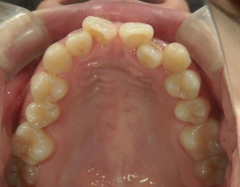

矯正歯科 治療前矯正歯科 治療前

矯正歯科 治療前

矯正_灰色.pngno.8_8495_治療前_上.jpg矯正_灰色.png